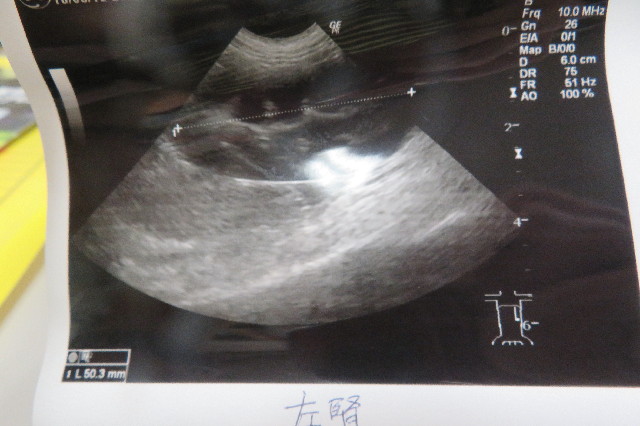

エコーの結果

謎の石がどこからきたものか気になるので、膀胱の炎症の具合と、膀胱に石がないか調べるためのエコーです。

【膀胱を横から見たところ】

膀胱の壁が晴れています。

●石はありません

腎臓に石があることもあるそうですが、“もにちゃん”の腎臓に異常はありませんでした。